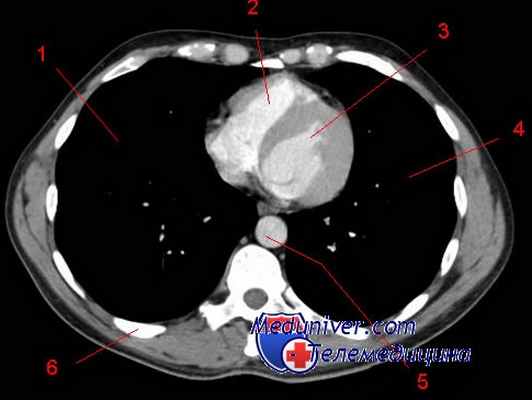

Определённые опухоли средостения имеют типичную локализацию (рис. 4.17). Опухоли из нервной ткани, как правило, расположены в заднем средостении. -

Типичные локализации различных опухолей и кист средостения и примыкающих к нему тканей:

1 — внутригрудной зоб; 2 — гиперплазия вилочковой железы (тимома); 3 — аневризма аорты; 4 — увеличенные лимфатические узлы (лимфома); 5 — тератоидная опухоль; 6 — дермоидная киста; 7 — целомическая киста (в том числе дивертикул перикарда); 8 — жировая парастернальная грыжа и липома средостения; 9 — поражённые метастазами лимфатические узлы; 10 — бронхиальная киста; 11 — гастроэнтерогенная киста; 12 — невринома; 13 — менингоцеле

Липомы чаще находятся в правом кардио-диафрагмальном углу. Опухоли вилочковой железы располагаются в верхних отделах переднего средостения и нередко протекают с синдромом миастении (прогрессирующей мышечной слабости). В средних отделах переднего средостения чаще развиваются тератомы, лимфосаркомы и лимфогранулематоз. Саркомы средостения относят к крайне злокачественным и быстрорастущим опухолям, которые рано прорастают и сдавливают органы средостения. При саркомах часто развивается синдром верхней полой вены. Принципиальным для клинической картины опухолей переднего средостения является сдавление сердца и верхней полой вены, а для заднего средостения - сдавление пищевода и нервных образований.